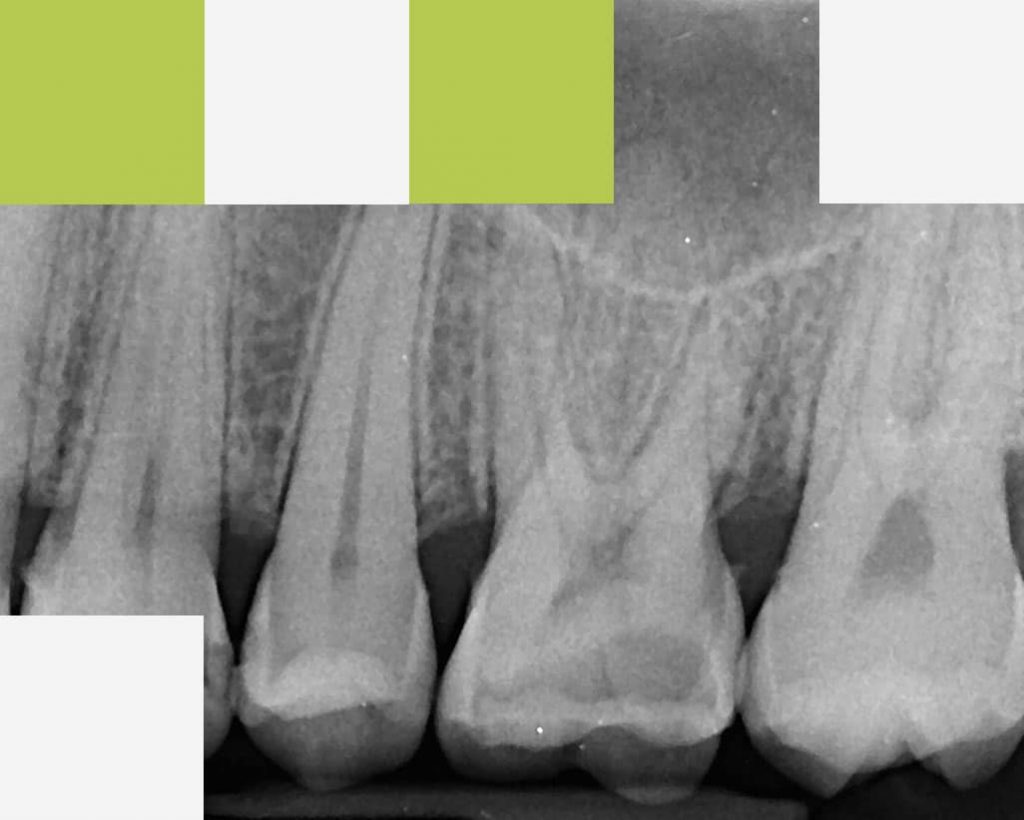

2. Radiografia digitală retroalveolară

Radiografia retroalveolară (periapicală) se realizează pentru un dinte, sau un grup de doi maxim trei dinți, pentru a evidenția dintele în întregime, la dimeniuni reale: coroana, rădăcina și osul în care această este ancorată. Radiografia retroalveolară este recomandată în tratamentele endodontice, parodontale, chirurgicale, pentru vizualizarea rădăcinii sau a coroanei dintelui.